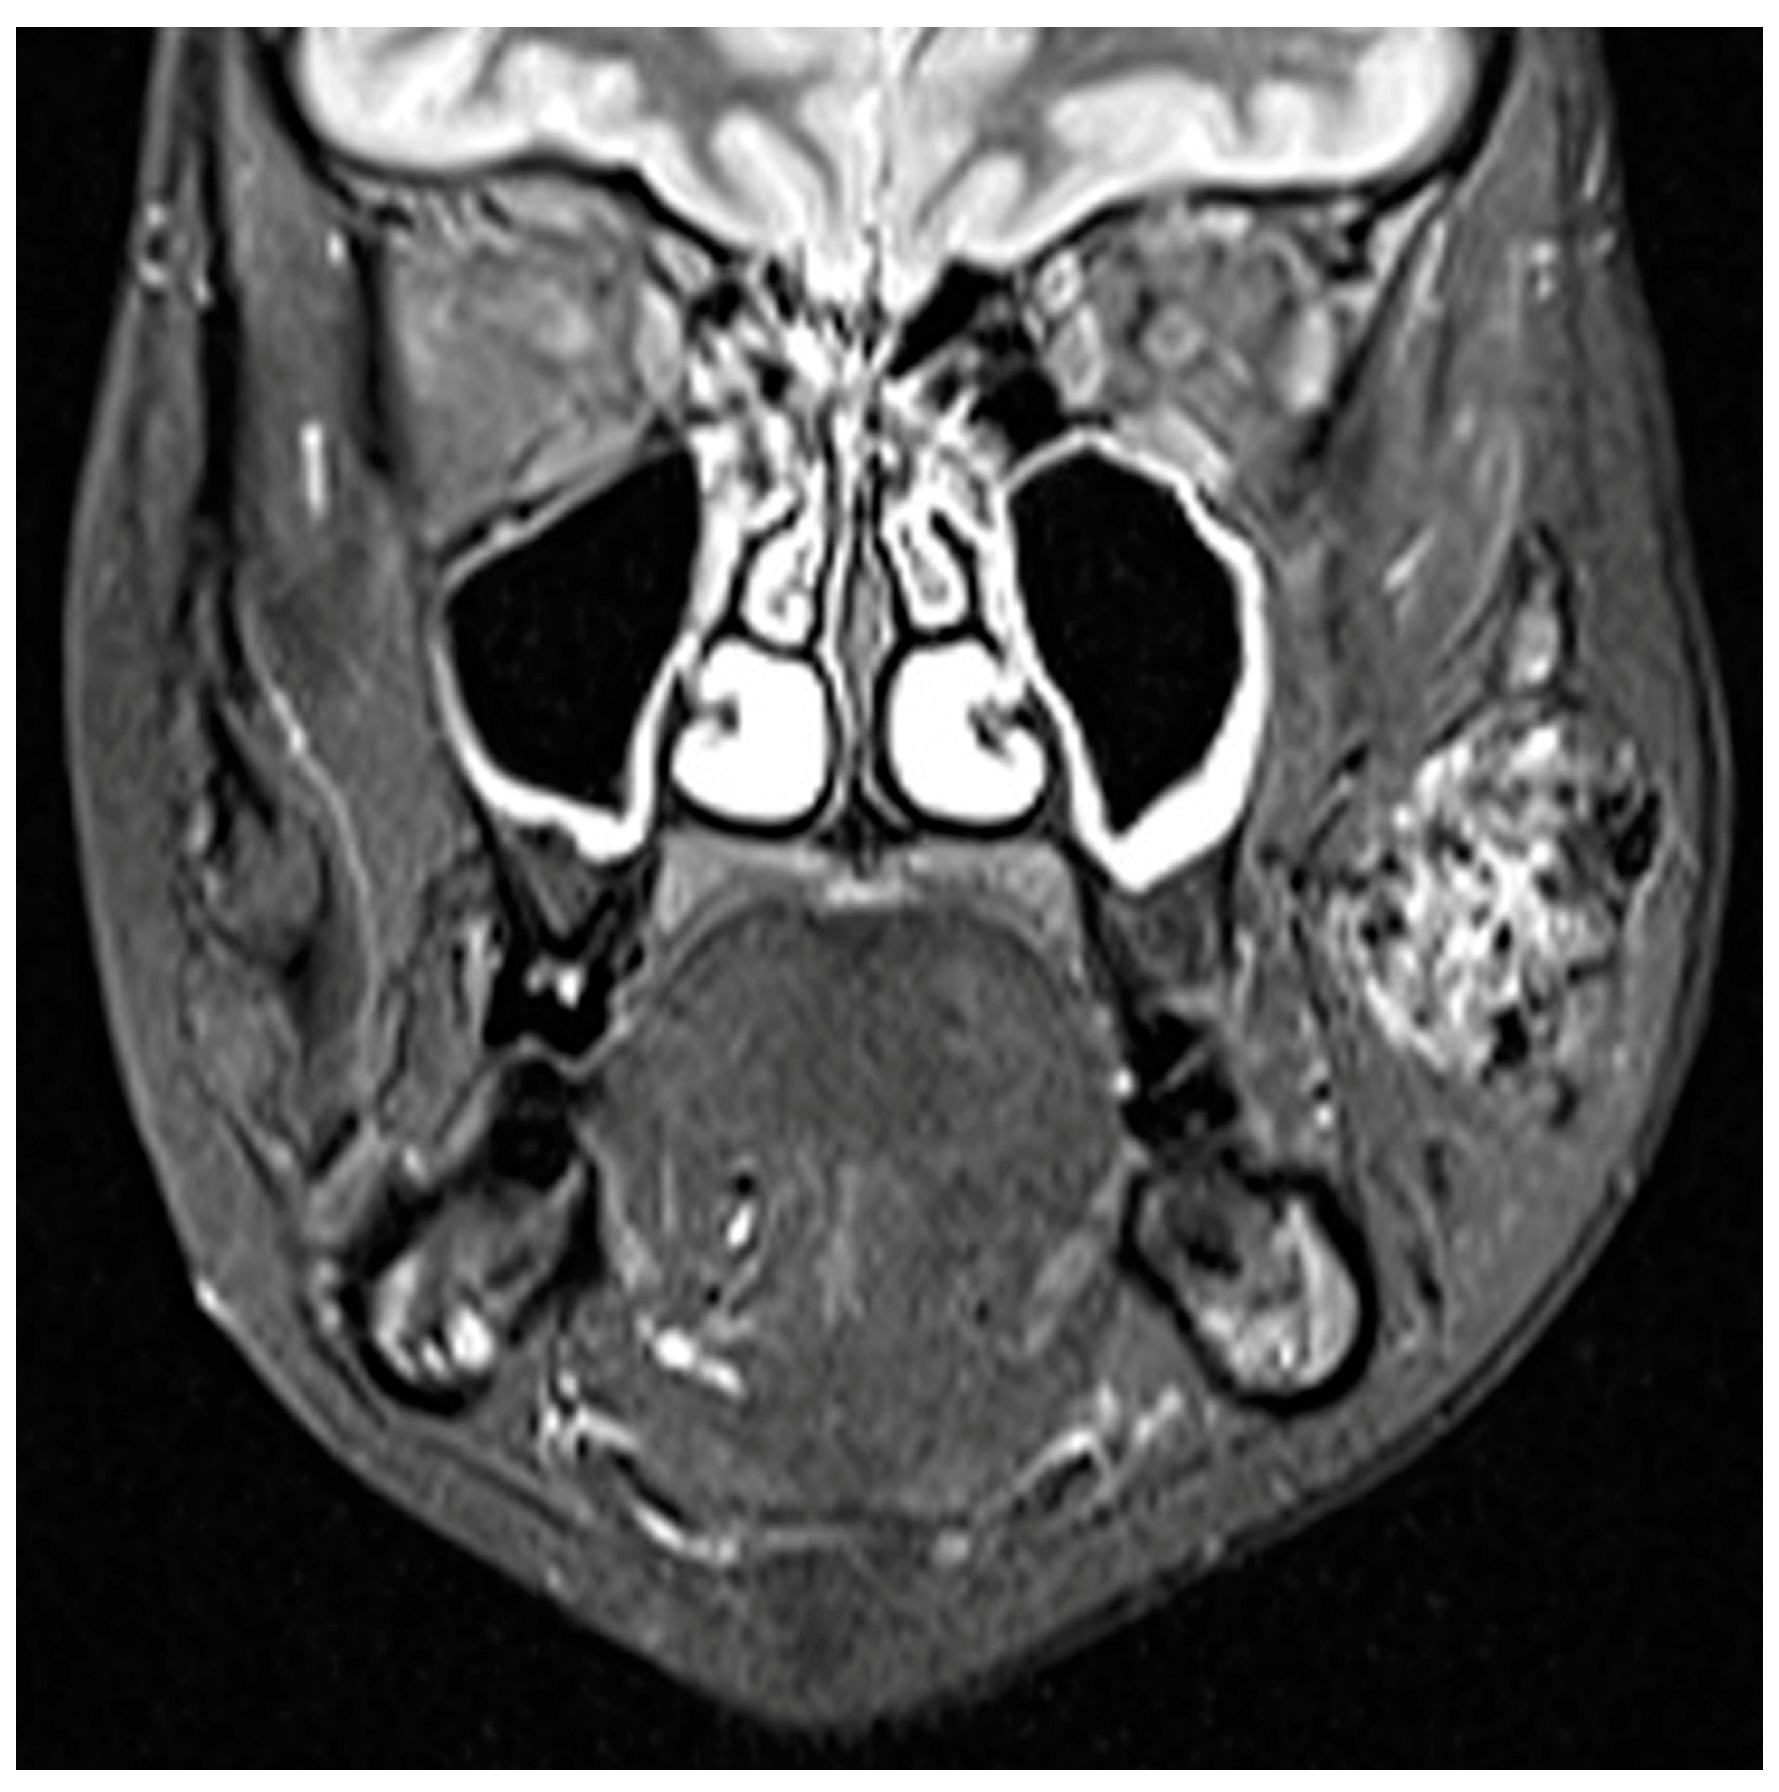

3.1. Venous Malformations

3.1.1. Clinical Data

3.1.2. Diagnosis

3.1.3. Therapy